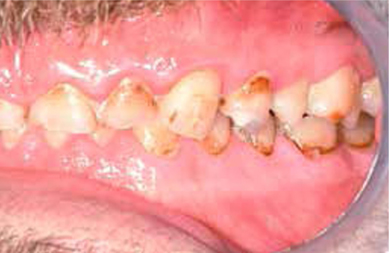

Bij het extraoraal onderzoek zie ik een lichte hypertrofie van de m. masseter. Intraoraal tref ik een ernstig versleten dentitie aan waarbij de slijtage niet passend bij de leeftijd kan worden genoemd (afbeelding 2-7 en tabel 1) .

Afbeelding vergroten

Afb. 6

Lateraal aanzicht links.